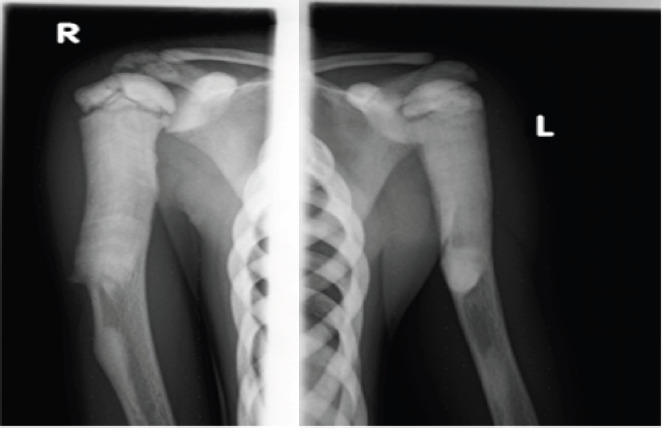

Case presentation: The patient is an eight-year-old girl who came to our hospital with complaints of bilateral arm swelling and visual disturbances for four years and a history of fracture of the left lower extremity two years before presentation. Physical examination revealed nontender bilateral arm swelling and a shorter left leg. The laboratory tests were within normal limits. A skeletal radiograph showed typical radiographic features of osteopetrosis.